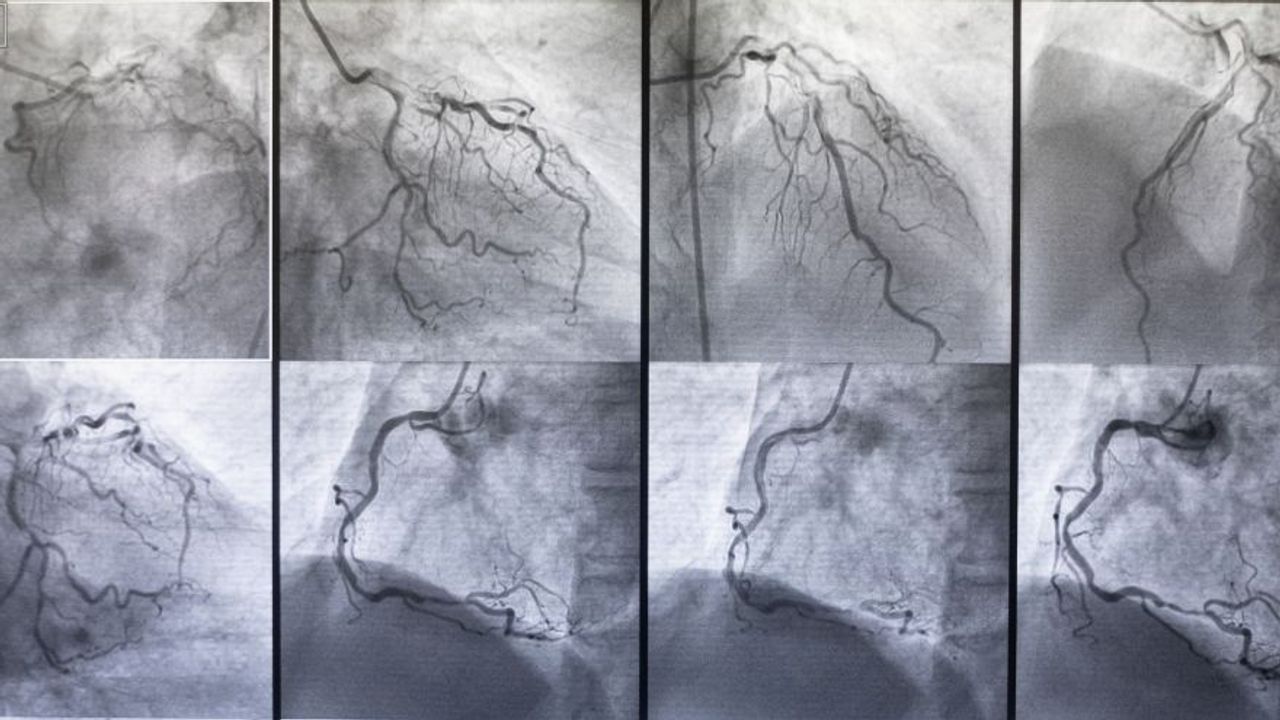

Anjiyografinin genellikle bilekten yapıldığını anlatan Prof. Dr. Okuyan, işlem sırasında kalbe giden damarların net şekilde görüntülendiğini ve tıkanıklık saptanırsa balon ya da stentle hemen açıldığını söyledi. Bazı hastalarda ise damar yapısına bağlı olarak bypass ameliyatının daha uygun olabileceğini belirtti.

Prof. Dr. Okuyan, her hastanın damar yapısının birbirinden farklı olduğunu, kimi damarların elastik ve kısa, kimilerinin ise daha kireçli veya ince olduğunu söyledi. Bu nedenle tedavi yönteminin kişiye özel seçildiğini ifade etti.